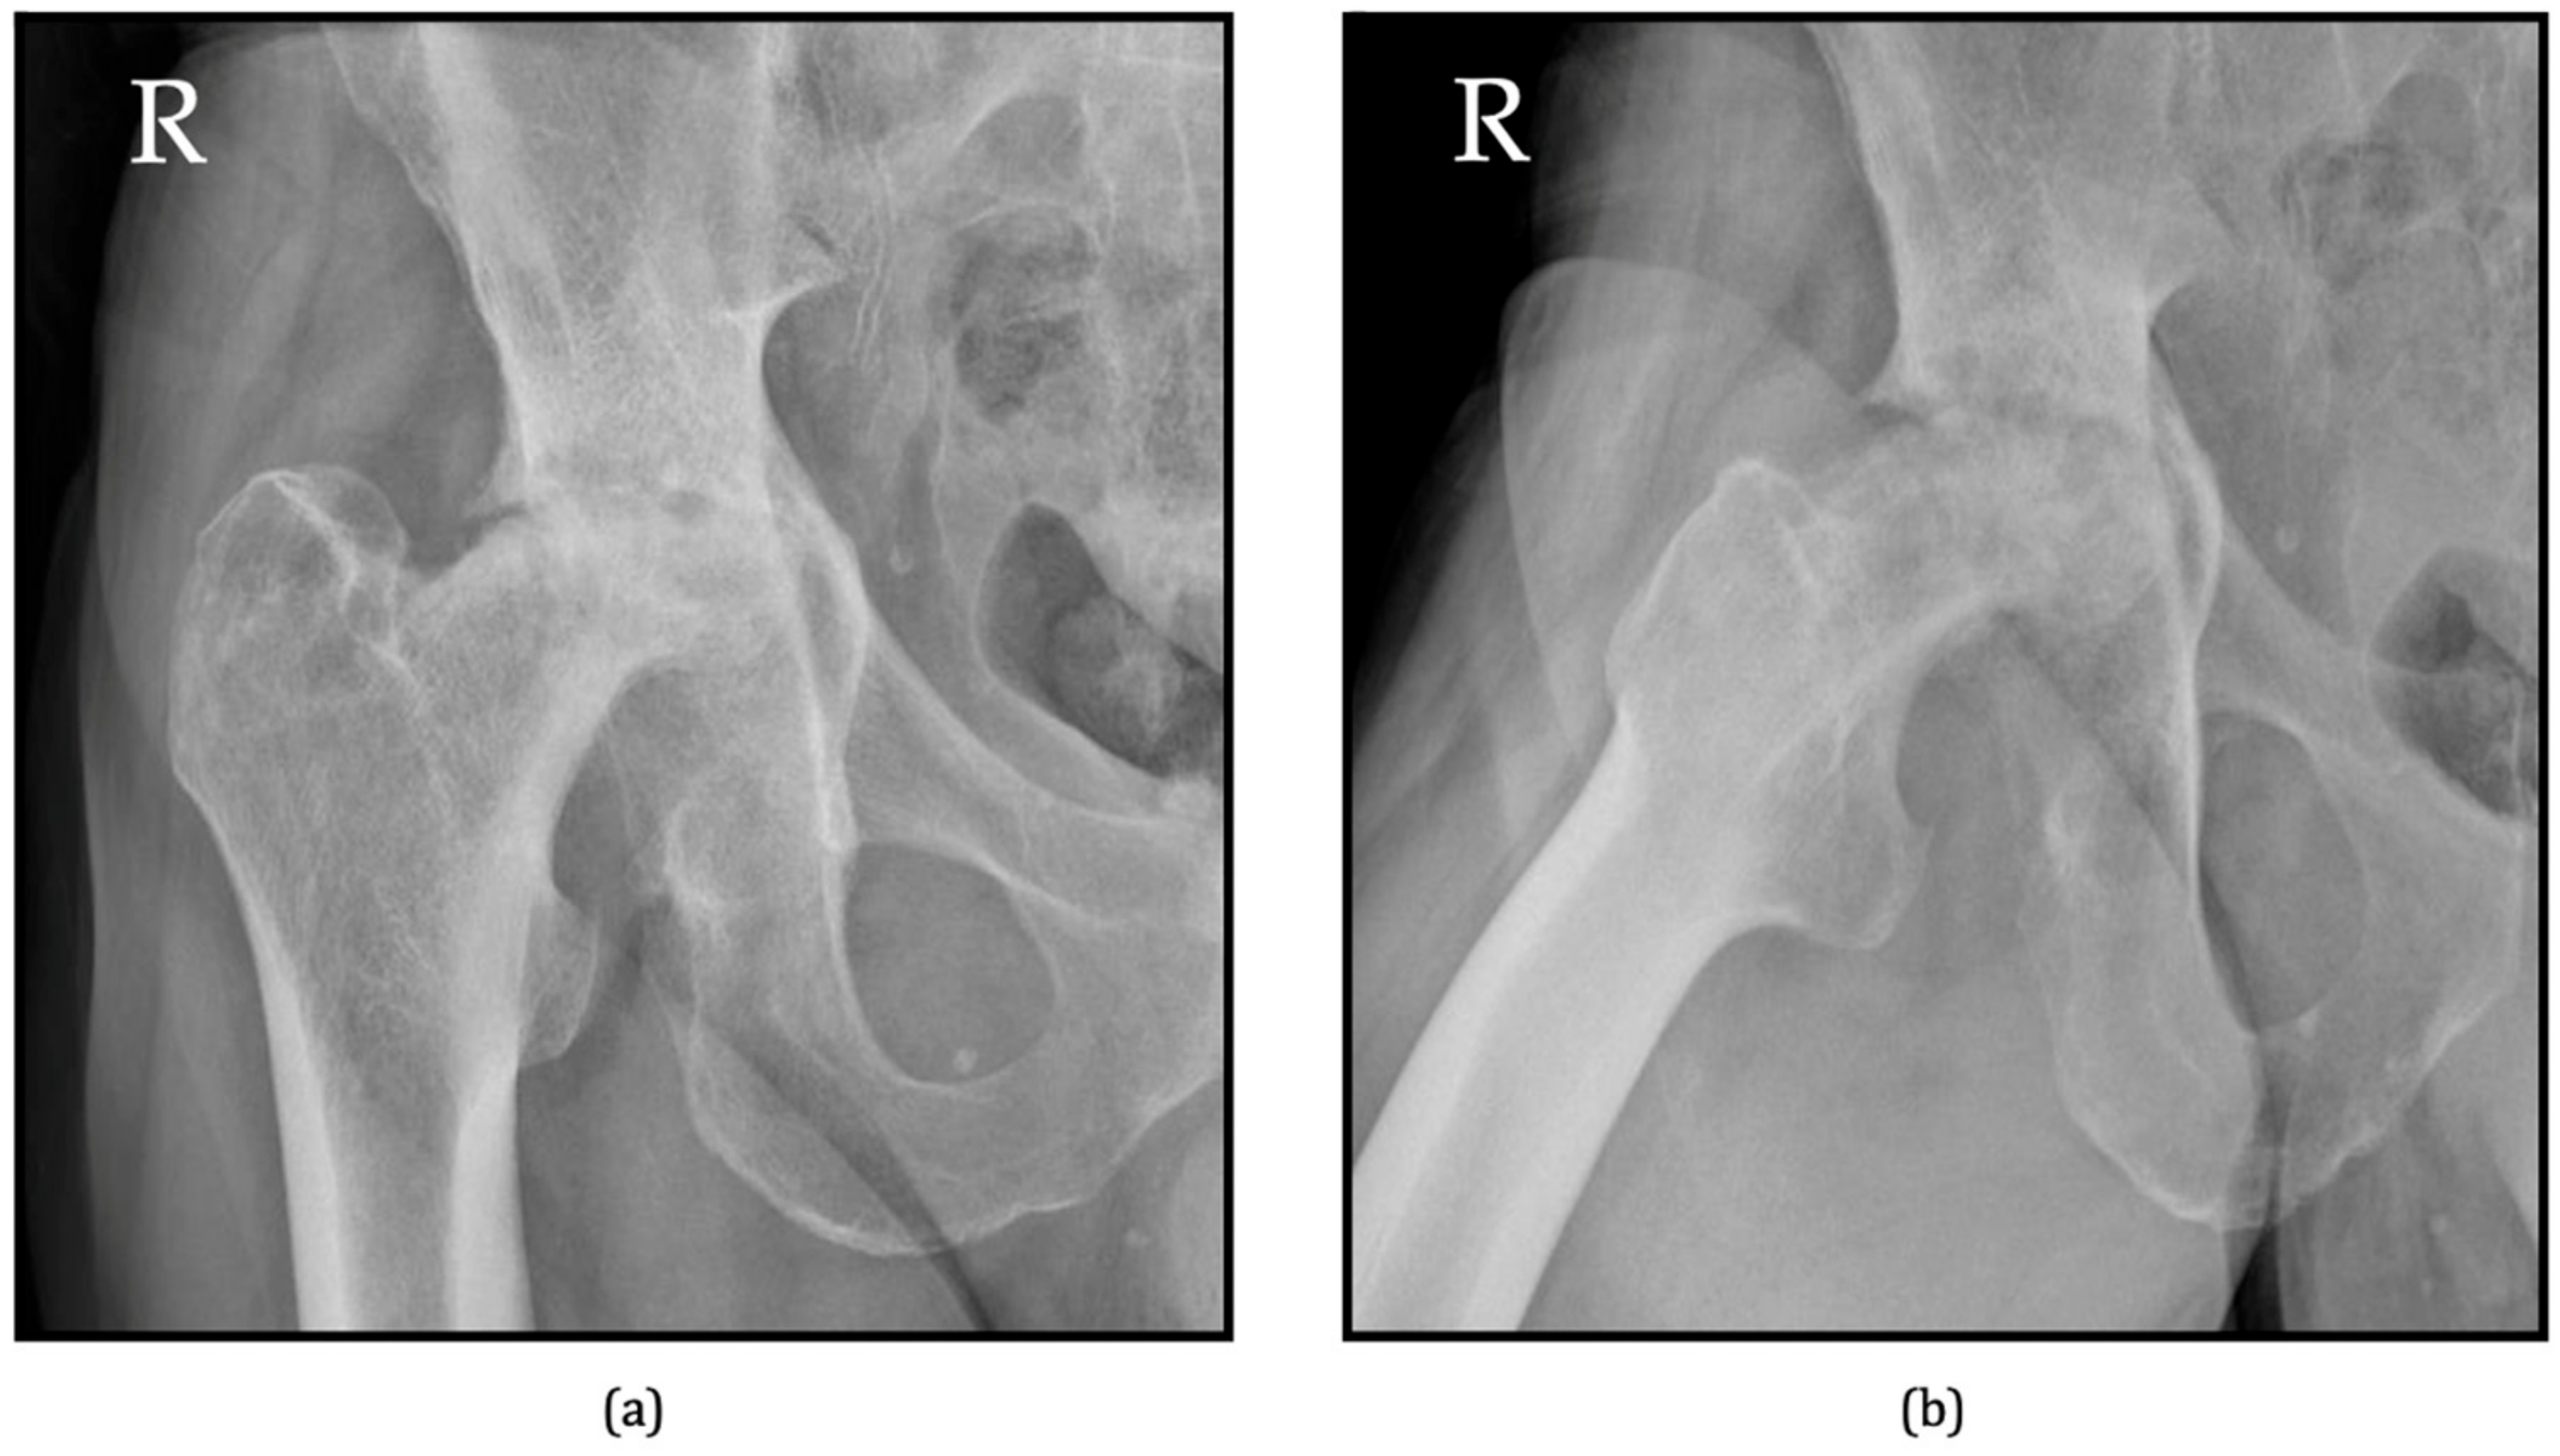

6.1. Radiographs

| Pivec R, Johnson AJ et al. [43] | 2013 | Type 1 | Rapid joint space narrowing, no rapid femoral head dissolution or acetabular bone loss. |

| Type 2 | Severe joint degeneration, rapid progression with femoral head and acetabular destructive changes within 6–18 months. | ||

| Yasuda T, Hashimura T et al. [17] | 2020 | RPOH Type 1 | Joint space narrowing with no femoral head destruction within 12 months after onset of hip pain. |

| RPOH Type 2 | Rapid joint space narrowing and femoral head destruction within 12 months after onset of hip pain. | ||